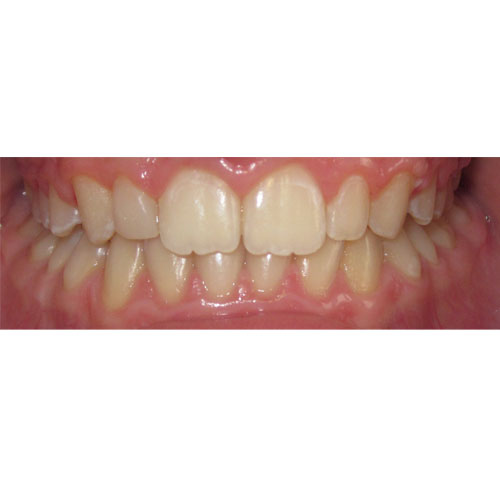

Nasze rezultaty